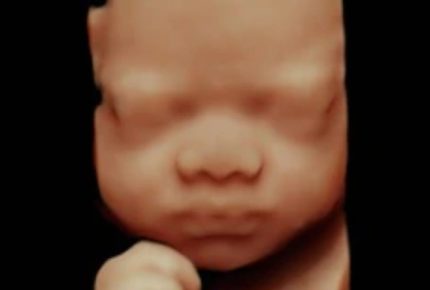

24-32+ weeks 4D Scan

If you just cannot wait until baby is born to find out whether they will have Dad’s nose or Mum’s chin then either of our Can’t Wait to Hold You packages are the perfect choice. Suitable from 24-32 weeks. After 32 weeks may be a challenge as baby has a bit less room in there and gets ready to make its entrance!

• Viewing your baby in HD 4D live during the scan which is a live motion video of baby in your bump

• View your baby in HD 4D live during the scan which is a live motion video of baby in your bump